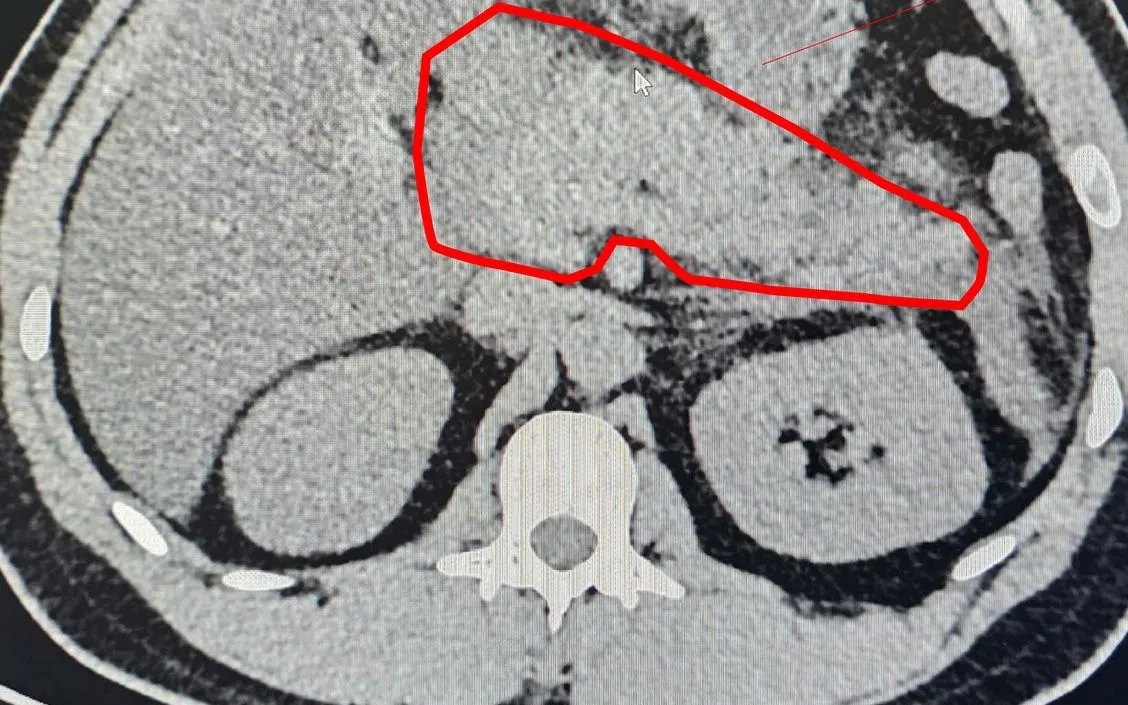

Hình ảnh chụp cắt lớp vi tính cùng các xét nghiệm cận lâm sàng xác định bệnh nhân bị viêm tụy cấp nặng do tăng triglycerid máu. Ngay sau đó, người bệnh được điều trị tích cực theo phác đồ chuyên môn, bao gồm nhịn ăn giai đoạn đầu, nuôi dưỡng tĩnh mạch, bù dịch, giảm đau, giảm tiết dịch vị, kiểm soát mỡ máu và theo dõi sát các chức năng sống. Khi tình trạng lâm sàng cải thiện, bệnh nhân được chuyển dần sang chế độ ăn phù hợp.